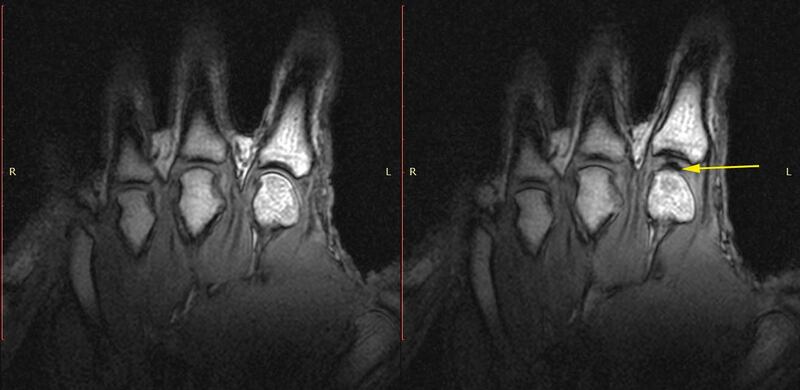

In 2015, however, Greg Kawchuk of University of Alberta and collaborators used an MRI scanner to record what was happening in the finger of a volunteer who was a frequent knuckle-cracker.

In the images, you can see the sudden appearance of a bulge in the knuckle as it is cracked.

This is the result, Kawchuk and colleagues wrote, of the formation a bubble, which persisted for some time afterward, and whose creation might be responsible for the cracking noise. They posited that the bubble generated a pressure wave in the fluid, producing a sound. However, it was not clear how that wave could be powerful enough to make the distinctive crack.

That could help their results line up with those of Kawchuk, whose images showed the existence of a bulge in the knuckle long after the sound had passed. The bubble only needed to contract by 30 to 40 percent to make that popping noise, said Barakat, leaving a gas pocket intact, albeit a smaller one than what is visible in the MRI.